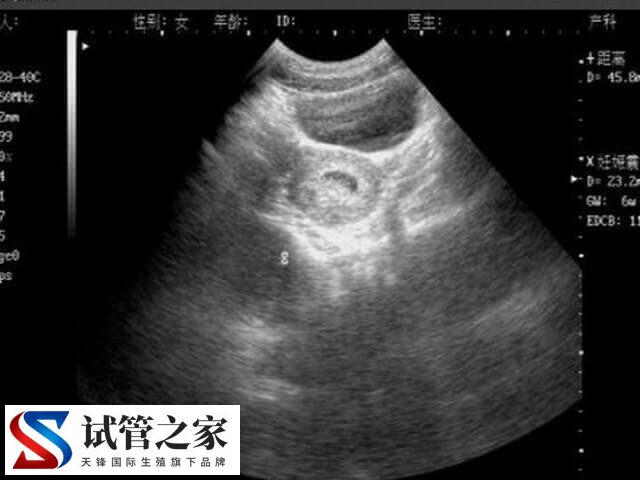

乳腺低回声对试管婴儿的影响

乳腺低回声对试管婴儿的影响主要取决于乳腺低回声结节的性质和严重程度。如果患者对此比较感兴趣的话,那么可以参考下列内容了解。